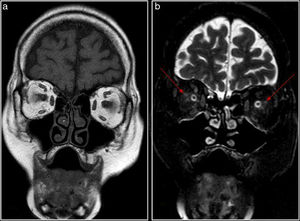

Se realiza una RM craneal y orbitaria (Philips Intera 1.5T) que muestra discreta leucoencefalopatía hipoxicoisquémica. Tras administrar gadolinio, en las secuencias T1 con saturación de grasa se observa realce orbitario perineural mal delimitado en la vaina de ambos nervios ópticos y en el tejido graso retrobulbar adyacente (figs. 1 y 2). Dicho hallazgo ha sido descrito en ACG con afectación visual, por lo que, en el contexto de la paciente, sin evidencia de otras patologías inflamatorias o neoplásicas, se sugirió este diagnóstico.

El hallazgo que se ha descrito con más frecuencia (menos de 10 casos en la bibliografía) es el realce perineural que afecta a la vaina del nervio óptico y a la grasa perineural (figs. 1 y 2), que sugiere cambios inflamatorios: perineuritis óptica1–4. En algún caso se ha descrito extensión hasta el quiasma (neuropatía óptica isquémica posterior5,6. En un paciente en el que se realizó biopsia perineural se confirmó tejido fibroadiposo con múltiples arterias con inflamación mural por linfocitos y células gigantes7.

Los hallazgos de la ACG en RM son poco frecuentes, inespecíficos y variables, lo que puede retrasar el diagnóstico y el tratamiento. Esta entidad puede provocar, con menor frecuencia, manifestaciones visuales por otras causas vasculares (oclusión de la arteria central de la retina, oclusión de arteria ciliorretiniana, infarto del lóbulo occipital)7. Sin embargo, una exploración de RM orbitaria de alta resolución, incluyendo secuencias STIR, T2 y T1 con saturación grasa y gadolinio intravenoso, puede demostrar captación perineural en una localización característica de NOIA que, en el contexto clínico adecuado, orienta hacia el diagnóstico precoz de ACG.